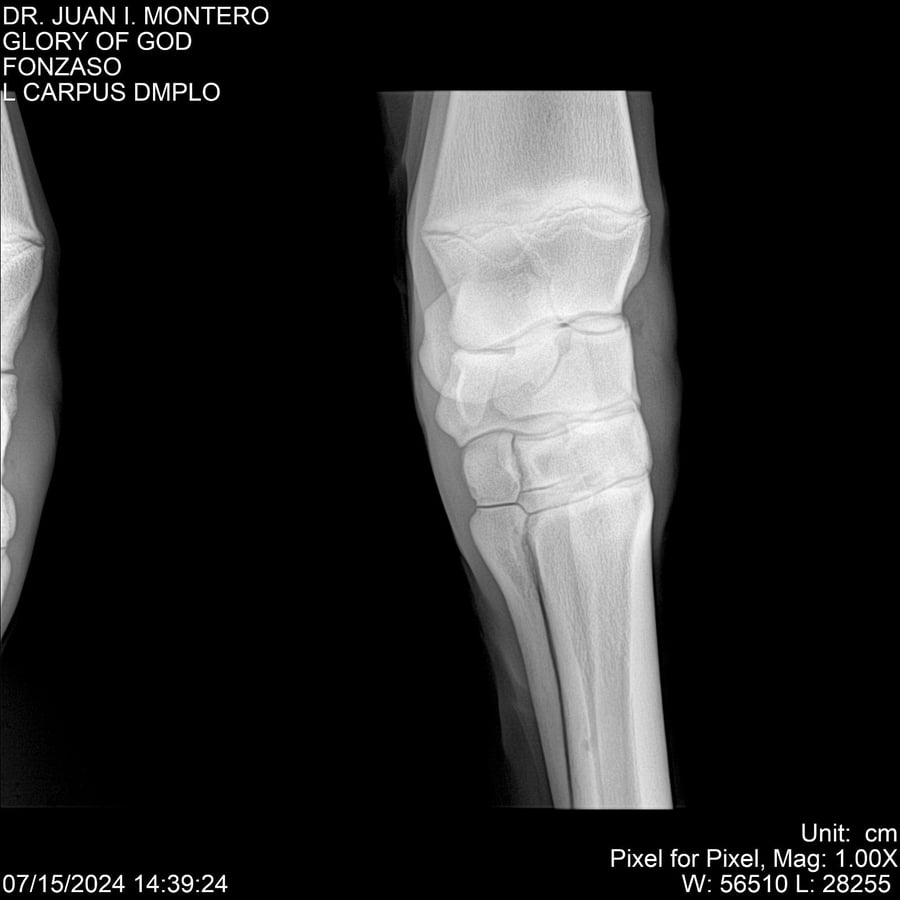

LOTE 10, GLORY OF GOD 🔥 🔥 🔥 Lote Anterior Volver al remate Lote Siguiente Ficha Contacto Montevideo - Ficha del Lote Identificador: #281389 Categoría: Yeguarizos Montevideo - 115 Visualizaciones ClicData Contacto Empresa: Abelenda N. R., Walter Hugo Nombre*: Teléfono* : E-mail* : Mensaje Enviar Registrese gratis Este contenido Exclusivo está disponible sólo para usuarios registrados Ingresar